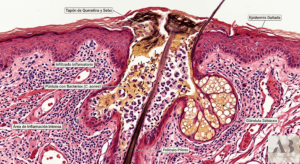

La función barrera cutánea es una estructura fisiológica esencial que protege a la piel de agresiones externas y regula el equilibrio hídrico interno. Está compuesta principalmente por el estrato córneo, los lípidos intercelulares y el manto hidrolipídico. Su integridad garantiza que la piel pueda ejercer su rol inmunológico, sensorial, termorregulador y protector de manera adecuada.